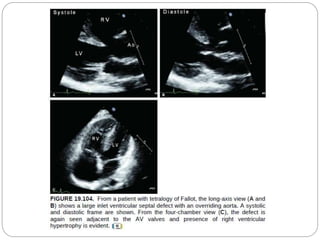

 Apical 4 chamber view

 Assess right and left ventricular size and function

 Right ventricular hypertrophy may be assessed by

measurement of the free wall of the right ventricle